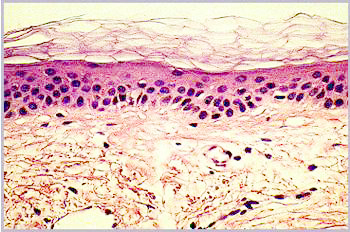

Neue Untersuchungsmöglichkeiten Die in-vitro-Hautmodelle eröffnen neue Wege, all dies Unzulänglichkeiten

zu vermeiden. Durch sukzessives Züchten einer Dermis aus Fibroblasten

und einer Epidermis mit Stratum Corneum aus Keratinocyten entsteht innerhalb

von 5 Wochen ein Ganzhautmodell (Abbildung 4), das alle wesentlichen Schichten

der Haut enthält (7) (Abbildung 5).